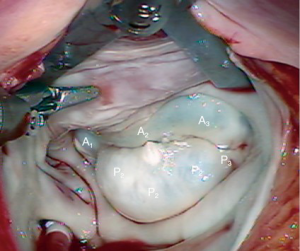

A 63-year-old man presented with symptomatic severe mitral regurgitation. Both trans-esophageal 3-D echocardiography and operative linear measurements showed a 25 mm long A2 anterior leaflet with a very wide (23 mm) prolapsing 30 mm long P2 posterior mid-scallop (Figure 1A,B). P1 and P3 were diminutive in height and width (Figure 2). A ‘haircut’ posterior leaflet-plasty was done to maintain leaflet-annular integrity, shorten and reduce the prolapsing P2 and preserve adequate tissue for coaptation.

The redundant, large P2 segment is best evaluated using ventricular saline pressure filling (saline test) (Figure 2). The height (length from annulus) of P1 and P3 are used to guide the ultimate length of the remaining P2 segment. The end of P2 is resected horizontally (by the ‘haircut’ technique) to approximate the length of P1 and P3 (Figure 3). Any stable chords of good quality attached to P2 are identified and preserved along with a small leaflet segment. We propose three scenarios to reconstruct P2 during the leaflet-plasty.